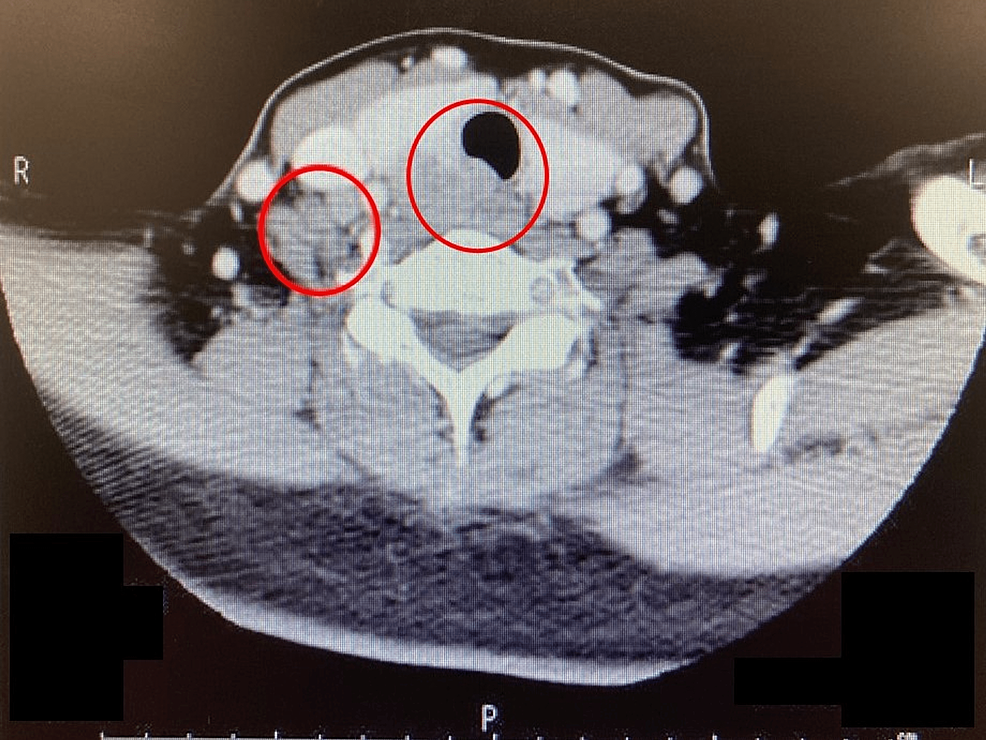

Figure 1 from Traumatic Tracheobronchial Laceration Causing Complete Tracheal Resection Anesthesia Management 1 the success rate of the procedure is reported as. Our primary objective is to describe the perioperative anesthetic management of patients with tracheal stenosis undergoing trr. Guardian suture and guardian roll. Tracheal resection with primary anastomosis is presently a surgical procedure performed in major tertiary centers, managed by an interprofessional team of anesthesiologists,. In recent years, we have evolved. Tracheal Resection Anesthesia Management.